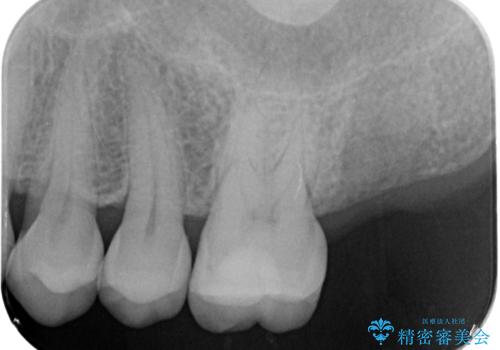

- 噛むと歯が疼いて痛い、と根管治療を希望され来院されました。

精査した結果、上顎奥歯は歯が割れてしまっており、根管治療ではなく抜歯の対象でした。

歯の抜去後、しっかりと咬合機能を回復するためインプラントを用いた治療を行っていきます。